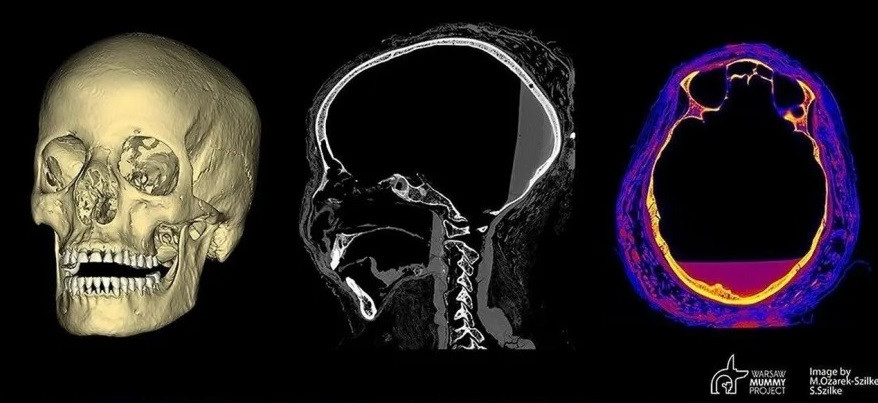

Trong nghiên cứu đầu tiên được công bố về xác ướp, các nhà nghiên cứu đã sử dụng hình ảnh chụp X-quang và chụp CT để xác định một số bó cơ quan ướp xác trong bụng của "Quý bà bí ẩn". Họ cũng cho rằng có thể nhìn thấy một thai nhi được bảo quản kém, khoảng 28 tuần tuổi thai, trên các lần chụp X-quang và chụp CT. Ảnh: Wikimedia Commons.

Trong nghiên cứu thứ hai, nhóm nghiên cứu đề xuất rằng lý do không thể xác định rõ ràng xương thai nhi là do tử cung của người mẹ thiếu oxy và trở nên có tính axit theo thời gian, về cơ bản là "làm chua" thai nhi. Về sau, nhóm nghiên cứu cho rằng đã tìm thấy bằng chứng về ung thư vòm họng có khả năng gây ra cái chết của bà nghi nghiên cứu hộp sọ. Ảnh: thearchaeologist.

Các thành viên trong nhóm nghiên cứu đã kiểm tra hơn 1.300 lát cắt hình ảnh CT thô của xác ướp được chụp vào năm 2015 để xác định xem có bằng chứng nào về việc mang thai hoặc ung thư hay không. Ảnh: Public Domain.

Kết quả kiểm tra của nhóm nghiên cứu chỉ ra "Quý bà bí ẩn" không hề mang thai và không mắc ung thư. Trong đó, thứ được cho là thai nhi thực chất là một phần của quá trình ướp xác. Ảnh: worldatlas.

Nhóm nghiên cứu cũng không tìm thấy bằng chứng rõ ràng nào về việc "Quý bà bí ẩn" mắc ung thư và chết vì căn bệnh này. Họ cho rằng, tổn thương ở hộp sọ của bà rất có thể xảy ra khi những người thợ lấy não ra trong quá trình ướp xác. Ảnh: joyvspicer.